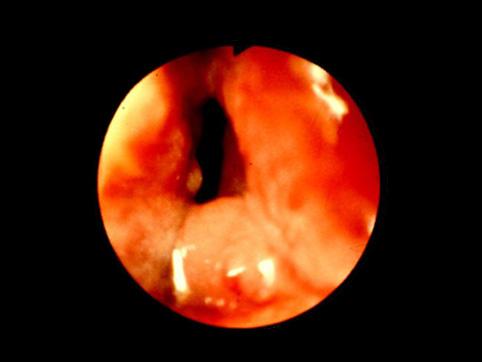

疾病(病理主体)的分类恶性淋巴系肿瘤/恶性淋巴瘤

部位(按器官分)十二指肠/下行脚

检查方法内窥镜

肿瘤最大直径35~40

多发性肿瘤(同一器官)有(同时性)